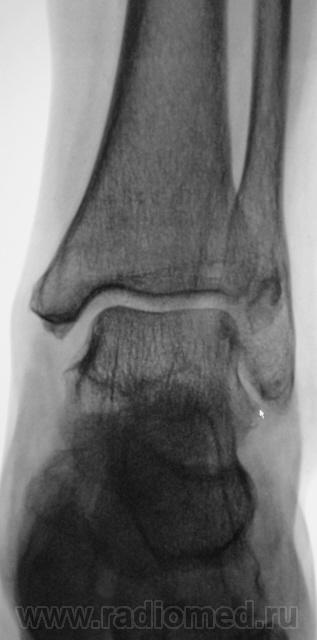

Травма. Пациент направлен врачом хирургом на рентгенографию голеностопного сустава.  Ваше мнение коллеги?

1. Не ясно, что здесь ( черная стрелка).

на консолидированный перелом Фолькмановского клина б\берцовой кости.

А, может быть, с учетом деформации малоберцовой кости, на боковой рентгенограмме, можно предположить, что, "это", откол фрагмента костной ткани от дистального эпифиза б/берцовой кости.